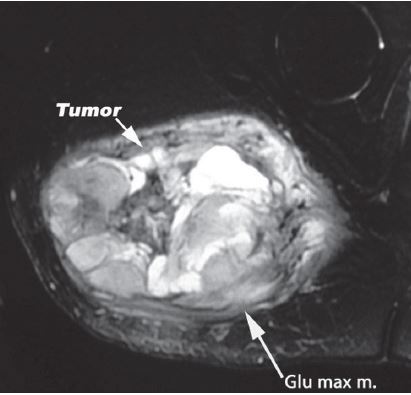

On this MRI, the tumor can be identified as the brightened portion on the left hand side of the image. Although it is the left side of the image, it is actually on the right side of the human.